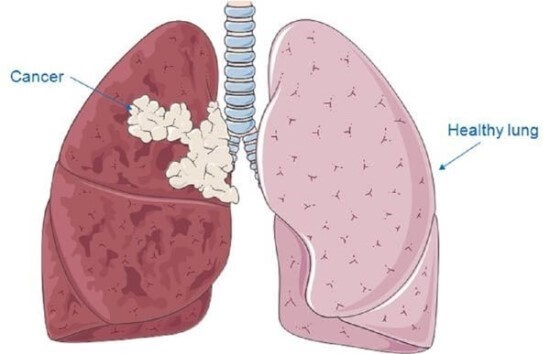

기흉은 폐의 표면과 흉벽 사이에 공기가 축적되는 상태를 말합니다. 이로 인해 폐가 충분히 팽창하지 못해 호흡 곤란과 통증을 유발합니다. 기흉은 자발적으로 발생할 수 있으며, 외상에 의해서도 발생할 수 있습니다.